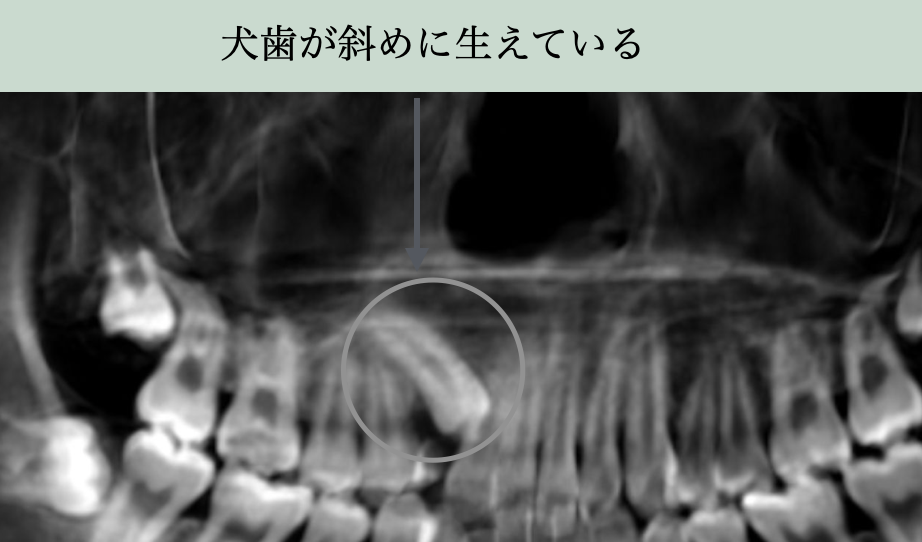

- 方向のずれ:犬歯が骨の中で斜め/横向きになっている

犬歯が骨の中で前に倒れてしまっていると、生える方向を見失ってしまうことがあります。

レントゲンではその位置や角度が確認でき、埋伏リスクを早期に見つけることが可能です。